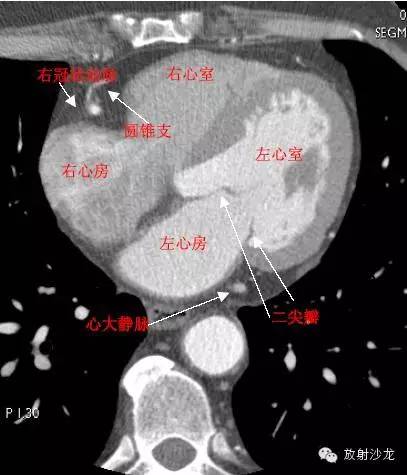

RA -Right Atrium右心房

LV -Left Ventricle左心室

RV -Right Ventricle右心室

MitralValve二尖瓣

RCA -Right Coronary Artery 右冠状动脉

ConusBranch右动脉圆锥支

GCV–Great Cardiac Vein心大静脉